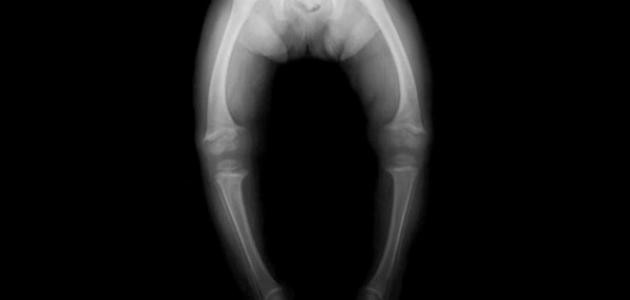

مسببات مرض الكساح

الأسباب العامّة لمرض الكساح